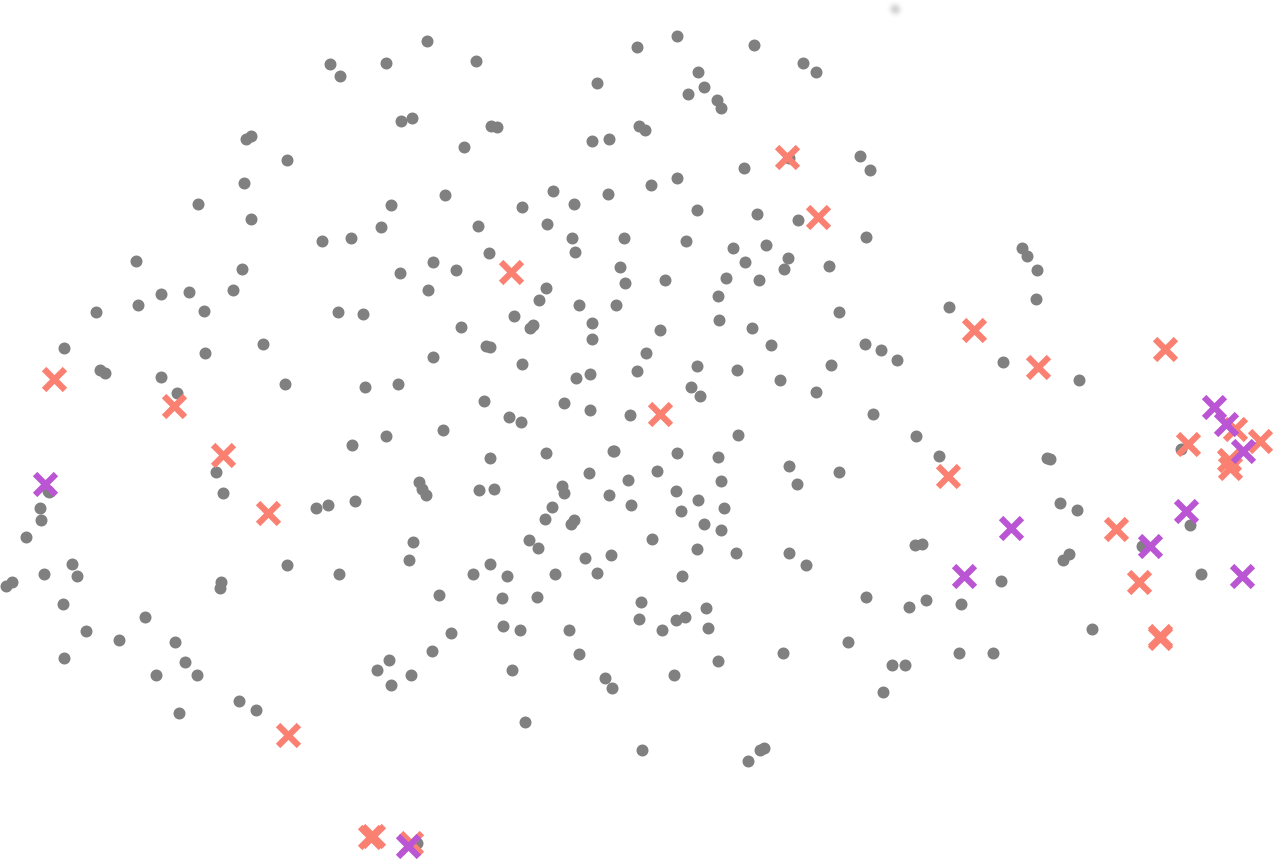

We argue that formulating a vertebral fracture detection as a naive classification problem is sub-optimal, more so in case of limited and unbalanced data regimes. Fig. 1a illustrates the TSNE representations of the latent features of one of the baselines in this work, viz. detecting vertebral fractures using a simple cross entropy loss using a convolutional neural network. Observe the resulting poor class-separation between healthy and fractured vertebrae. We attribute this to the wide variation in vertebral shapes: a healthy lumbar vertebra is ‘more different’ from a healthy upper-thoracic vertebra than a fractured lumbar vertebra. Moreover, there exists a ‘gradation’ among vertebral fractures, further obfuscating a clear shape-based separation (cf. Fig. 1b).

Figure 1: Illustrating fracture grades: (a) TSNE visualisation of latent representations learnt by formulating fracture detection as a simple classification problem, resulting in poor separability. (b) An example selection of the three classes of vertebrae studied in this work, healthy, grade-2 fracture, and grade-3 fracture.

In this work, we aim to incorporate the gradual shape variations, courtesy of the fracture grades, into the training process of a classifier by explicitly adjusting the latent space. Deep learning models are believed to generate useful representations as a byproduct of the task they are trying to solve. However, this is not the case in low-data regimes as shown in Fig 1a. Representation learning or metric learning can be used to learn efficient latent representations in such scenarios. Siamese networks [15] using contrastive loss and Face-Net [14] with its triplet loss are examples of standard metric learning frameworks wherein representations of similar entities are clustered together while those of dissimilar ones are pushed apart.